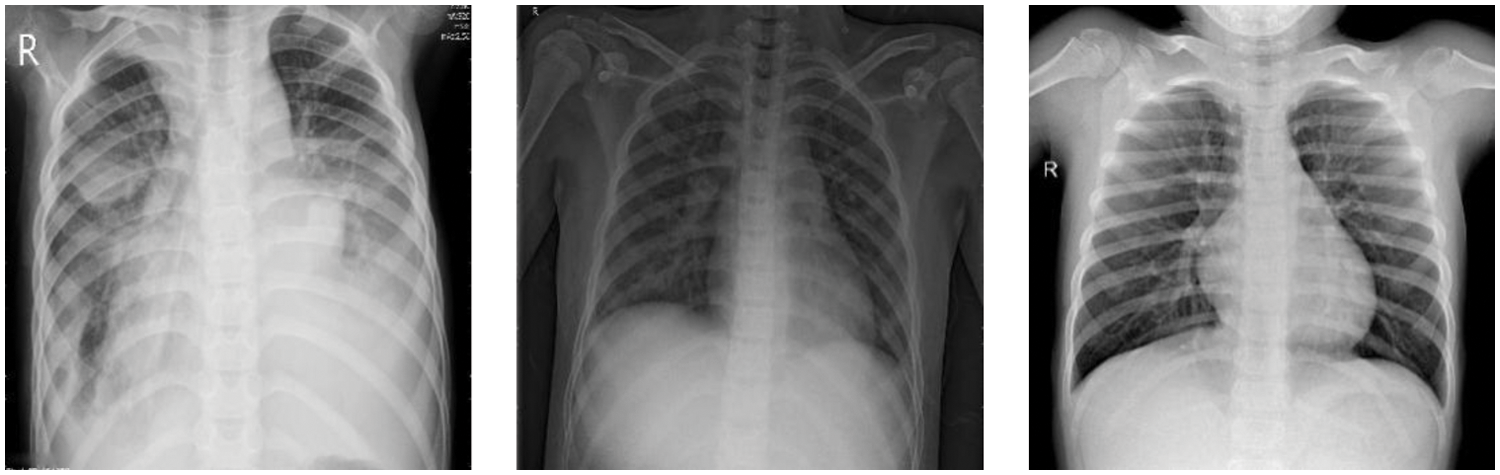

With the rapid development of Deep Learning (DL), the DL-assisted pneumonia diagnosis has been widely researched [5]. As one of the most powerful kinds of DL, Convolutional Neural Network (CNN) can handle the raw images directly and extract the feature of images for further diagnosis [6,7], and it has been widely used in the field of medical image [8]. As shown in Fig. 1, there is very little difference between abnormal sample 1 and normal sample 1, and the difference between normal sample 1 and normal sample 2 is very obvious, which is consistent with the fine-grained characteristics with small differences between classes and large intra-class differences. Therefore, it can be determined that chest X-ray images of children with pneumonia have typically fine-grained characteristics. There is little difference in chest X-ray images between normal people and patients with pneumonia, and the chest X-ray images of patients with pneumonia are diverse [4], which leads to inefficient and unreliable diagnosis methods based on CNN. Therefore, it is of great significance to develop more powerful diagnostic methods to improve the performance of CNNs on children’s chest X-ray images.

Figure 1: Children chest X-ray images, from left to right, are abnormal sample 1, normal sample 1, and normal sample 2